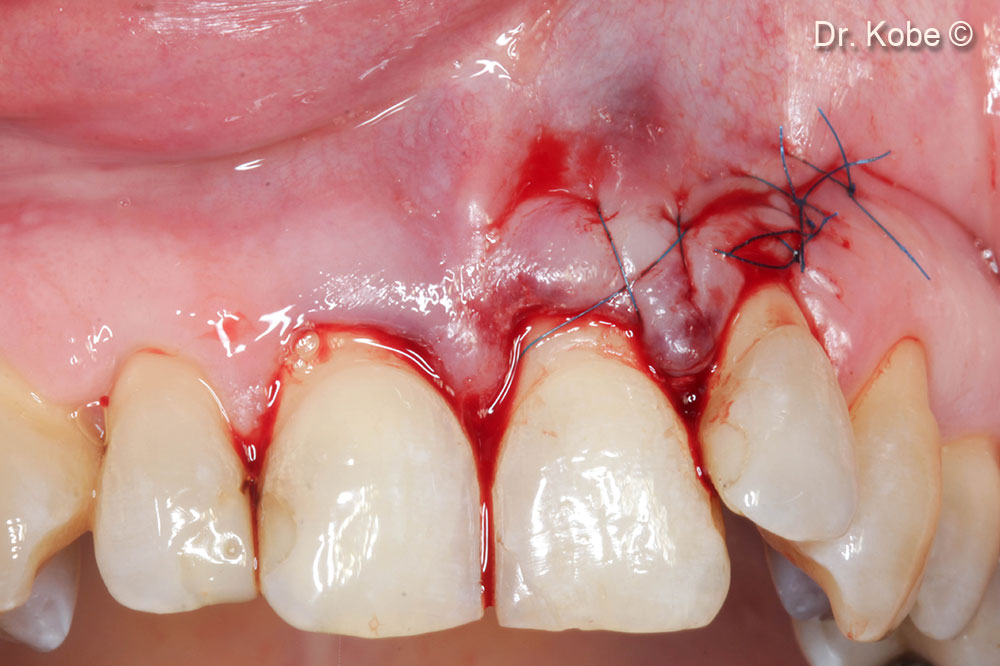

Vết khuyết được lấp đầy bằng Gel 40

Khâu vết thương bằng vết khâu đơn giản gián đoạn